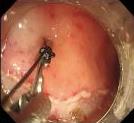

• 可旋转重复开闭软组织夹联合外科尼龙缝合线法闭合结直肠内镜黏膜下剥离术后缺损的临床应用价值

2025, 31(12):77-82. DOI: 10.12235/E20250091

摘要 (77) HTML (65) PDF 1.86 M (64) 评论 (0) 收藏

摘要:目的 探讨可旋转重复开闭软组织夹联合外科尼龙缝合线法(ROLM)闭合结直肠内镜黏膜下剥离术(ESD)后黏膜缺损的临床疗效。方法 回顾性分析2024年1月-2024年6月15例在南京医科大学附属常州市第二人民医院因早期结直肠肿瘤行ESD,并采用ROLM闭合黏膜缺损患者的临床资料。观察患者病灶相关情况(病灶部位、缺损最大径和术后病理)、手术相关情况(术后缺损成功闭合率、钛夹使用数量、ROLM缝合时间和住院时间)、术后并发症发生情况和术后随访情况。结果 术后缺损成功闭合率为100%。病灶长径3.0~6.0 cm,平均(3.7±0.8)cm。缺损部位:回盲部1例,升结肠6例,横结肠肝曲1例,降结肠2例,乙状结肠3例,直肠2例。术后病理为:管状腺瘤8例,黏膜下囊肿1例,管状绒毛状腺瘤5例,胃肠道间质瘤1例。钛夹使用数量为7~20枚,中位数为11(10,13)枚。ROLM缝合时间为13~37 min,平均(19.3±6.5)min。住院时间4~9 d,平均(6.5±1.2)d。术后无出血、穿孔、感染和消化道狭窄等并发症发生。术后3~6个月复查肠镜,手术创面均愈合良好。结论 ROLM能够安全、有效地闭合结直肠ESD后黏膜缺损。值得临床推广应用。